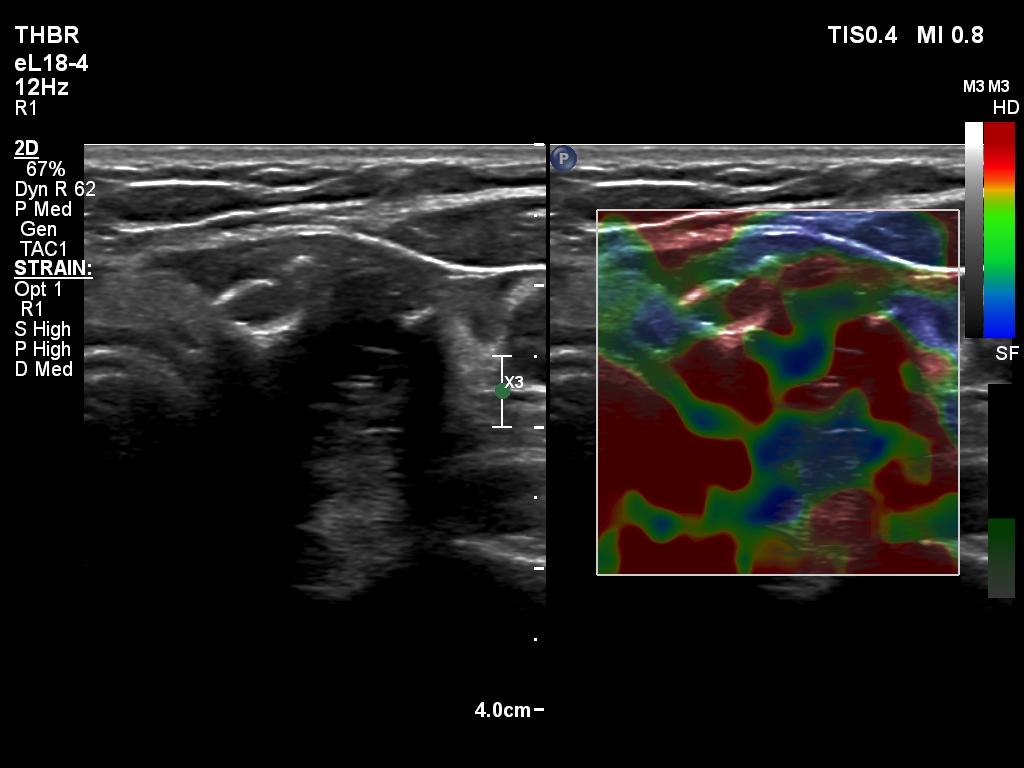

The composition of the nodule - case 2179 (ultrasonographic picture 21)

Right lobe, longitudinal scan

Middle-lower part of the left lobe, transverse scan, elastography. This is a non-specific pattern.